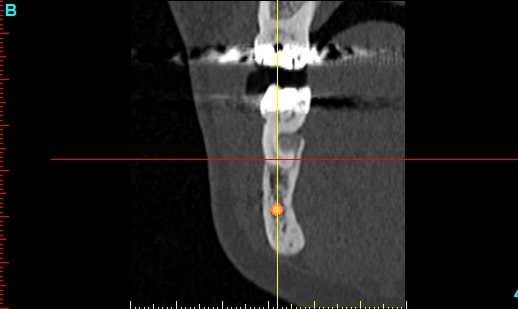

Patiente 58 ans à eu une chirurgie à visée esthétique et "fonctionnelle" adressée pour détartrage en urgence...je ne suis pas spécialiste mais je trouve que la greffe mentonnière est très bof

lésion apicale sur 42 risque de contamination sur la vis en regard..

Nous sommes d'accord pour la chirurgie mais secteur 4 il y a 2mm être là plastie et la mdble, ça ne me fais pas rêver

Nous sommes d'accord pour la genioplastie je me suis mal exprimé ce qui m'inquiète c'est la proximité de la greffe, pardon genioplastie et de l'infection de 42, d'une part et la mauvaise liaison de la genioplastie secteur 4, mais je suis peut-être pessimiste.

Plusieurs points: les vis de 15mm x 2mm qui transfixent c'est pas top, une seule plaque, qui plus est non réglable de chaque côté, c'est encore moins top. C'est une plaque de fracture.

En mandibulaire gauche c'est quoi ce fil d'osteosynthese? Un troisième fragment? En laissant l'apex de la 48 pile sur le trait d'osteotomie, je dis chapeau.

Pour la lésion de 42, ca peut être lié à la genio. Forage hasardeux? Mais je vote plus pour une lésion endo/paro